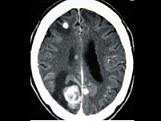

问题 乳癌脑转移时,常用的放射剂量为()

选项 A.25Gy/5次/1周 B.20Gy/5次/1周 C.10Gy/次 D.50Gy/25次/5周 E.30Gy/10次/2周

答案 E